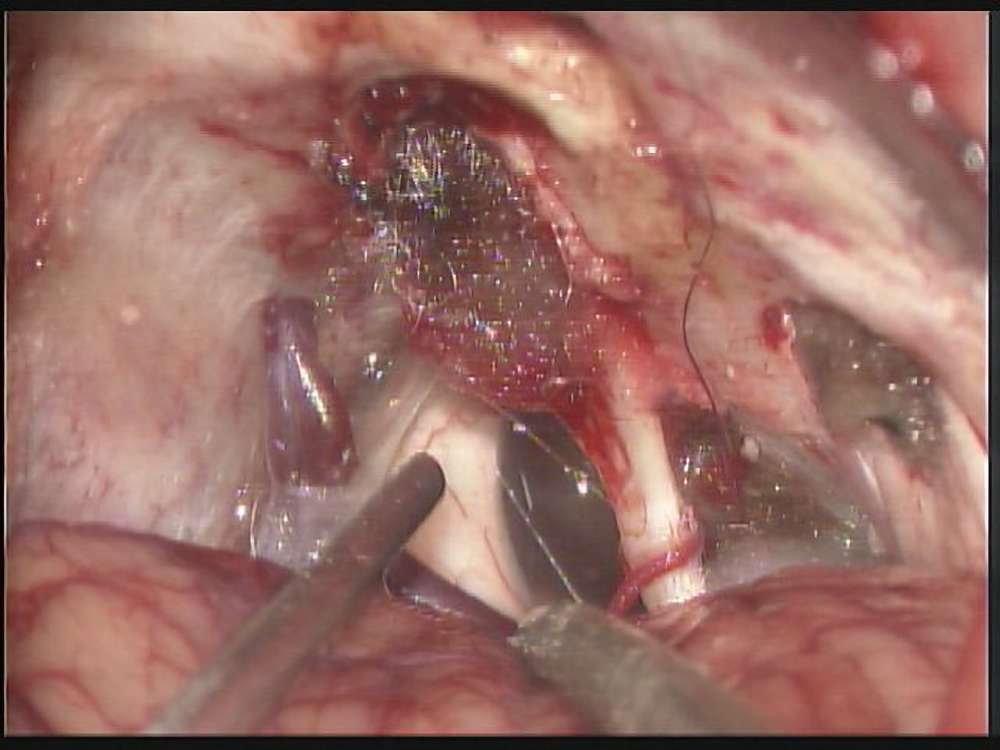

術中写真

摘出 前

摘出 中

摘出 後